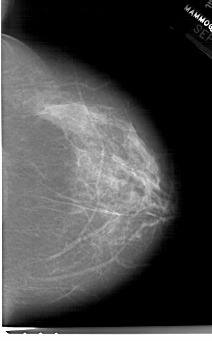

A_1514_1.LEFT_MLO

LEFT_MLO LINES 6871 PIXELS_PER_LINE 4501 BITS_PER_PIXEL 12 RESOLUTION 43.5 OVERLAY